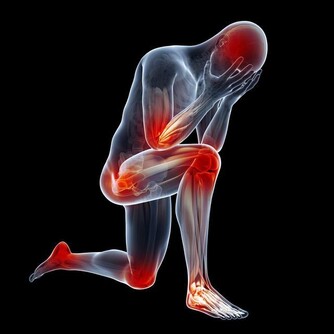

年輕人由於心肌梗死而離開的新聞一再發生, 特告知大家一個很重要的知識!自我心肺復甦。 關鍵時刻,能救自己一命。 假設現在時刻是17:50,忙忙碌碌的你上了一整天的班, 正在獨自開車回家的路上! 你感覺到非常緊張和不舒服…突然! 你感到胸口有一股劇痛,並且開始漫延到手臂和下巴, 可是,離最近的醫院大概還有一段路程。 更糟糕的是路況很差,你自己都不知道能不能撐得了那麽遠? 怎麼辦?你以前是曾經受過心肺復甦法CPR訓練, 但老師並沒教你怎麼給自己做急救? 獨處時,心臟病發作怎樣急救? 一個人若是心臟不能正常跳動,並且開始感到快要昏過去時, 他大概只有10秒鐘的時間,然後就會失去知覺,不省人事。 若是四周沒有旁人能幫忙急救, 患者要立刻把握這10秒鐘的短暫黃金時間自己救自己。

✿ 如何把握10秒鐘黃金時間? 首先不要驚慌,要不停咳嗽,用力的咳, 每次咳嗽前,都要先深深吸一大口氣, 然後,用力地、深深地、長長地、不停地咳, 好像要把胸腔深處的痰咳出來一般, 每間隔大約兩秒鐘,要做一次吸、一次咳, 一直要做到救護車趕到時,或者已經感到恢復正常,才能休息。 ✿ 答案: 1. 深呼吸,是要把氧氣吸進肺部。 2. 咳嗽,則是要以這個動作壓擠心臟, 進而促進血液循環,也可以幫它恢復正常脈搏。 ► 對心臟的擠壓如此急救, 可以讓心臟病發作患者有機會到醫院被救! 自我心肺復甦急救法,發出去吧。 說不定就因此救了他們一命!!! 請不要誤以為你的年齡少於25或30就沒有心臟病發作由於現今生活方式的改變, 心臟病發可發生在所有年齡組別的人。 關愛自己,關愛他人。 沒有比生命更可貴的了!轉出去,讓更多的人知道, 危急時刻可以互助!